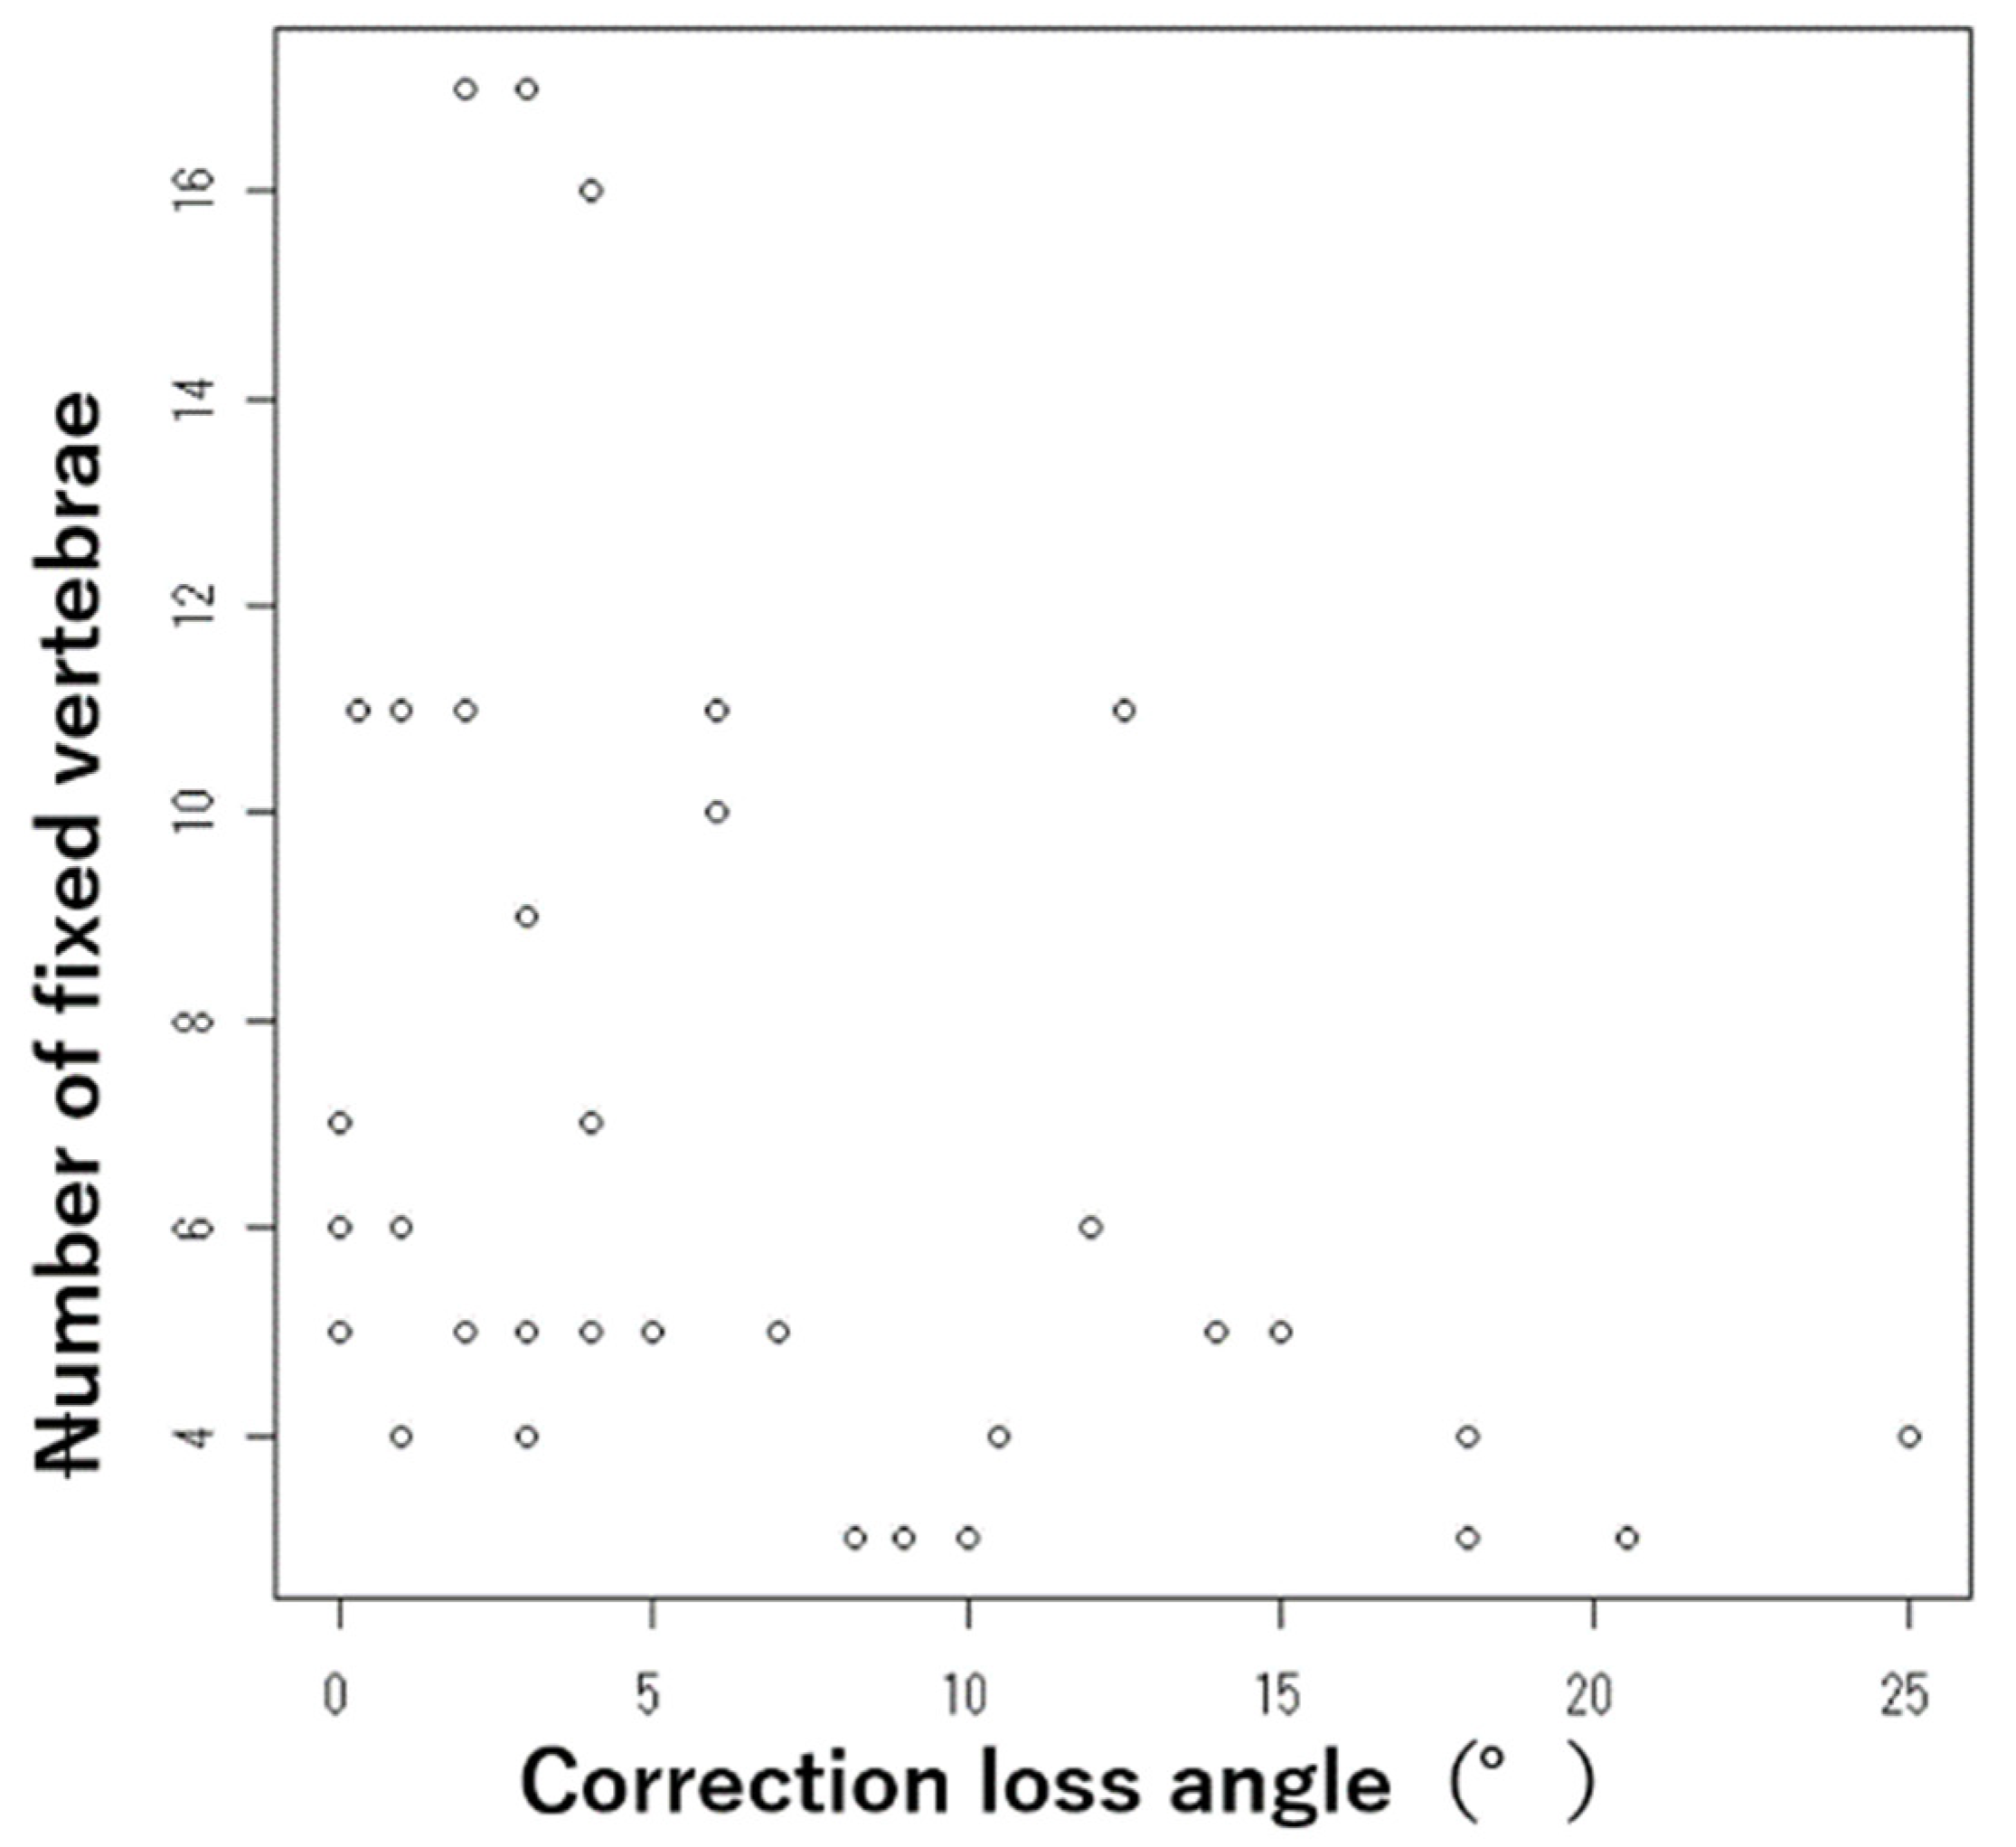

3. Results

| Number of fixed vertebrae | 6.9 ± 3.9 (3–17) | |

| Local kyphotic angle (°) | Pre-operative angle | 29.3 ± 17.4(−21–62) |

| Correction loss angle | 4.9 ± 8.4 (−15–20) | |

| Number of fixed vertebrae | 5.4 ± 4.5 | 7.4 ± 3.6 | 0.003 | |